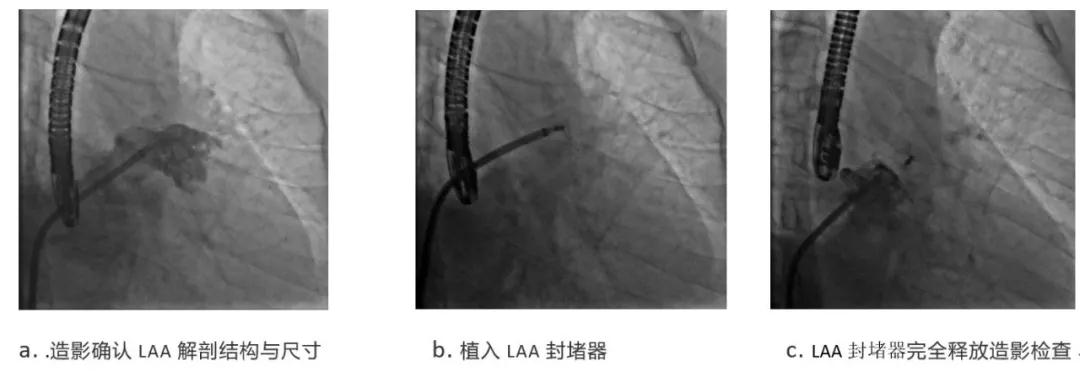

随后陶凌教授在会上分享两例患者术中造影及术后随访结果:第一位患者为65岁女性,左心耳为单腔结构,锚定区直径为26mm,第二位患者为58岁男性,左心耳为单腔结构,锚定区直径为21mm。二名患者均在全麻下经导管植入诺茂医疗研制的SeaLA®左心耳封堵器,封堵器规格分别为SL-LAA-3237和SL-LAA-2428。

病例一:

病例二: